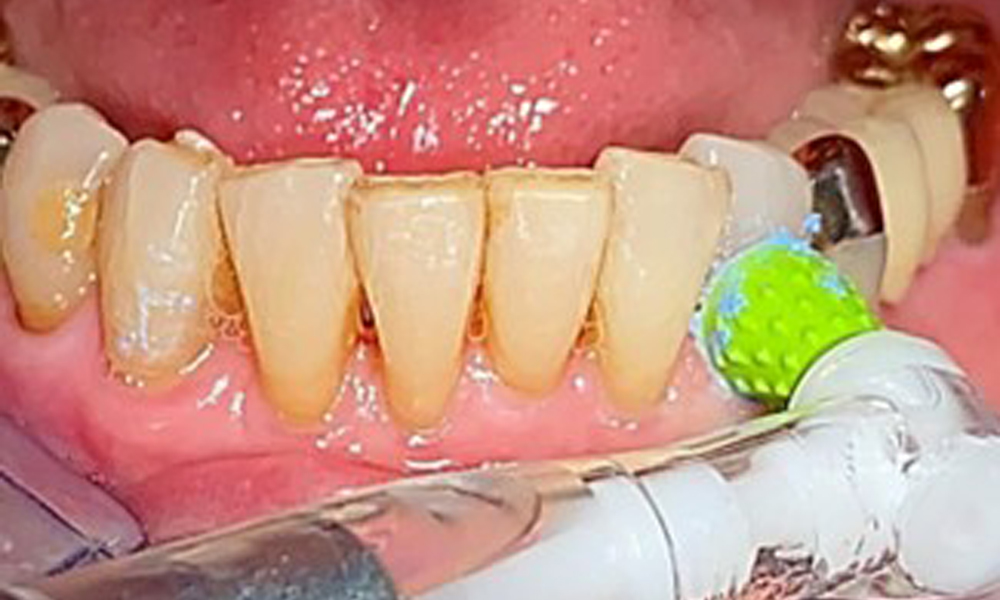

There are no limitations placed on the selective use of instrumentation during treatment due to the healthy general condition of the patient. Regular supragingival and subgingival instrumentation is essential to prevent disease progression (7). There are no restrictions on using instruments for mechanical biofilm removal from a general medical perspective, and removal should be performed as needed. (If the patient develops severe gingival inflammation, then there will be an increased tendency to bleed if an air polishing system is used due to the ASA 100 intake).

Sonic/ultrasonic, or conventional manual instruments may be used to remove calculus and concretions present on the natural teeth (8). Titanium or plastic curettes (Fig. 10), or a plastic or PEEK attachment (Fig. 11) during ultrasonic treatment, should be used to remove mineralized plaque from implants to avoid damaging the implant surfaces.

An air polishing system should be used with low-abrasive powder to remove biofilm from the restoration margins, interdental areas and implant surfaces (Fig. 12). Selective polishing (Fig. 13) should be used to smooth any less sensitive areas, as this decreases bacterial reattachment (9).